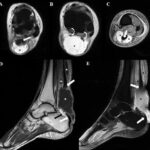

Are you looking for an affordable MRI of the Left Ankle With a Cartigram? Medifyhome offers competitively priced MRI and CT scans, partnering with top NABL-certified diagnostic centers and clinics. Our facilities ensure high-quality imaging and accurate results. An MRI of the left ankle with a cartigram (often called a cartilage-sensitive MRI sequence) provides detailed imaging to assess the cartilage, bones, tendons, and ligaments around the ankle joint. This type of MRI is beneficial for identifying cartilage injuries, tears, or degeneration, which are common in cases of arthritis or trauma. The cartigram sequence enhances the visualization of cartilage, allowing for a more precise diagnosis of cartilage health and integrity. This imaging can help guide treatment decisions, especially in cases where surgery or other interventions might be needed to restore joint function. Overall, it’s a powerful tool for accurately diagnosing and managing joint injuries and conditions in the ankle. To book an appointment for an MRI of the Left Ankle With a Cartigram scan, visit our platform, Medifyhome, or contact us at +919100907036 or +919100907622  for reasonable prices.